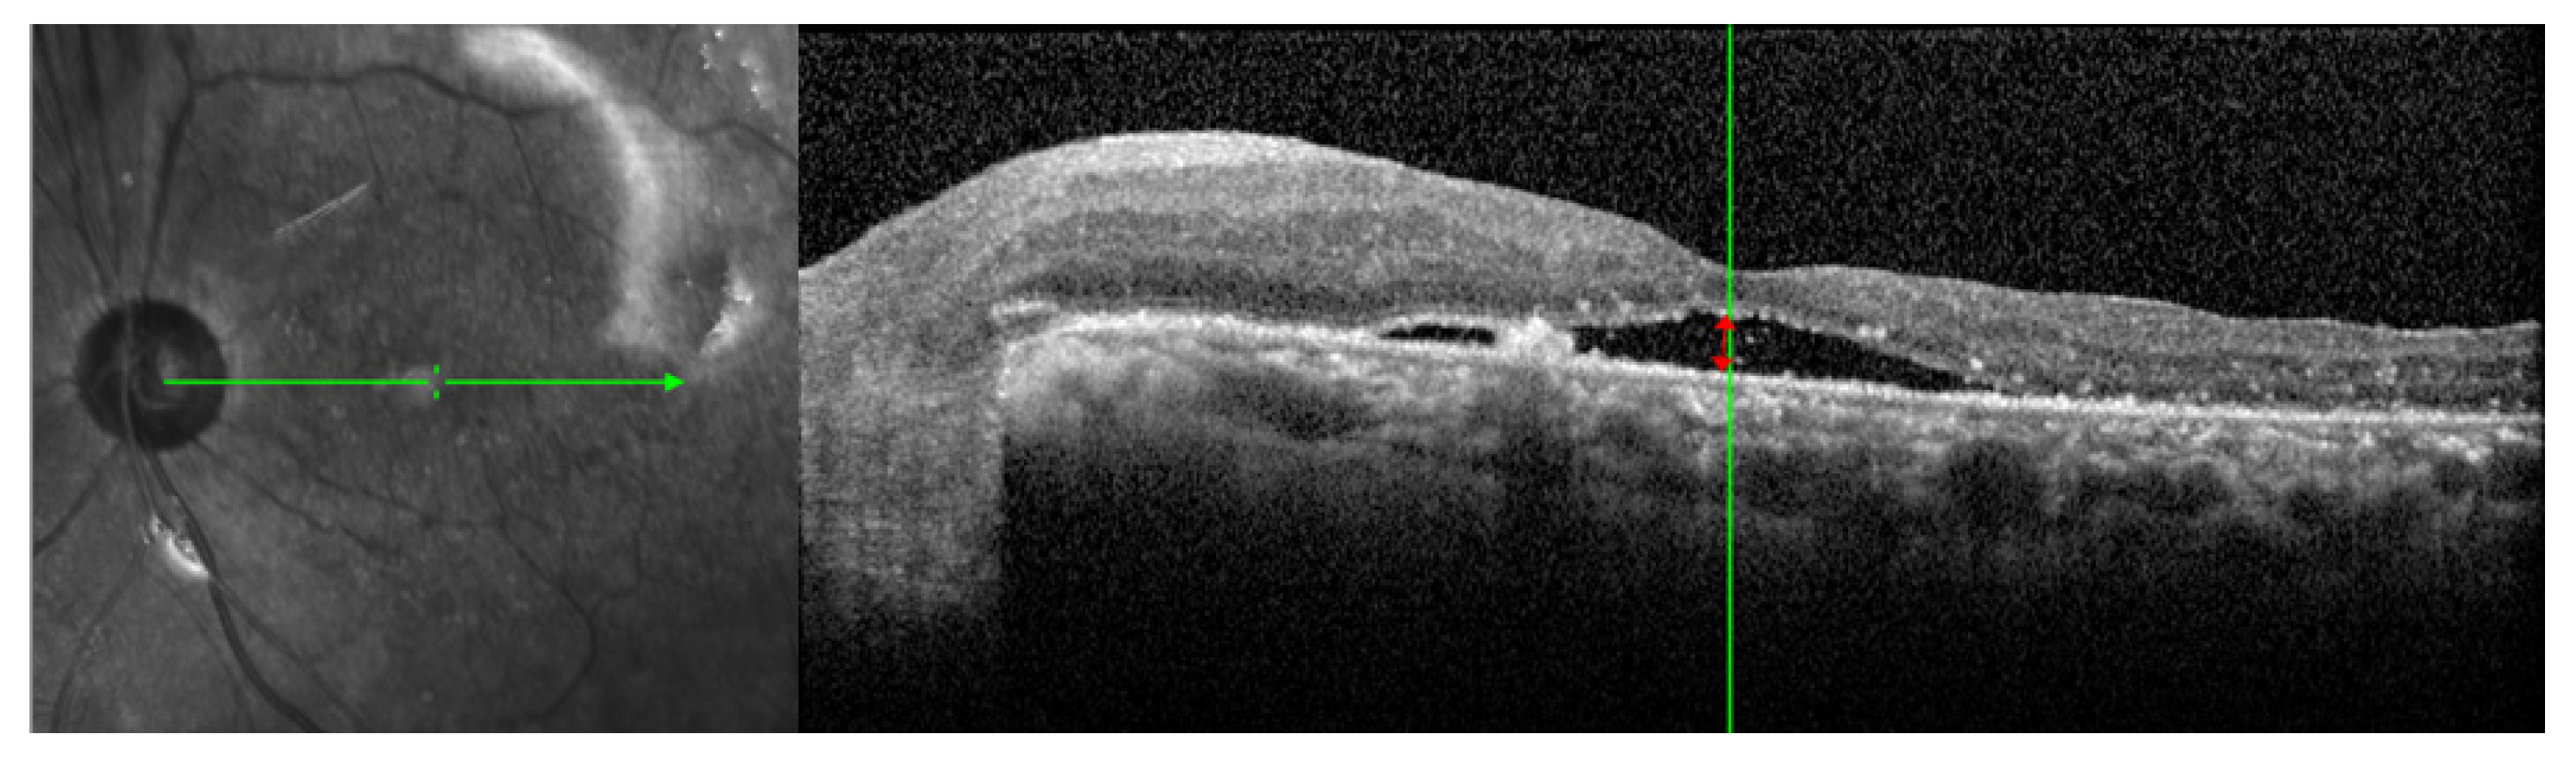

3.2. Duration of PSF and SRFH